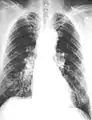

The abnormal chest x-ray and its interpretation remain the most important factors in establishing the presence of pulmonary fibrosis.[11] The findings usually appear as small, irregular parenchymal opacities, primarily in the lung bases. Using the ILO Classification system, "s", "t", and/or "u" opacities predominate. CT or high-resolution CT (HRCT) are more sensitive than plain radiography at detecting pulmonary fibrosis (as well as any underlying pleural changes). More than 50% of people affected with asbestosis develop plaques in the parietal pleura, the space between the chest wall and lungs. Once apparent, the radiographic findings in asbestosis may slowly progress or remain static, even in the absence of further asbestos exposure.[25] Rapid progression suggests an alternative diagnosis.

Asbestosis resembles many other diffuse interstitial lung diseases, including other pneumoconiosis. The differential diagnosis includes idiopathic pulmonary fibrosis (IPF), hypersensitivity pneumonitis, sarcoidosis, and others. The presence of pleural plaques may provide supportive evidence of causation by asbestos. Although lung biopsy is usually not necessary, the presence of asbestos bodies in association with pulmonary fibrosis establishes the diagnosis.[26] Conversely, interstitial pulmonary fibrosis in the absence of asbestos bodies is most likely not asbestosis.[11] Asbestos bodies in the absence of fibrosis indicate exposure, not disease.

Extensive fibrosis of pleura and lung parenchyma

Severe pleural fibrosis with focal calcification

61-year-old working industrially with asbestos for decades